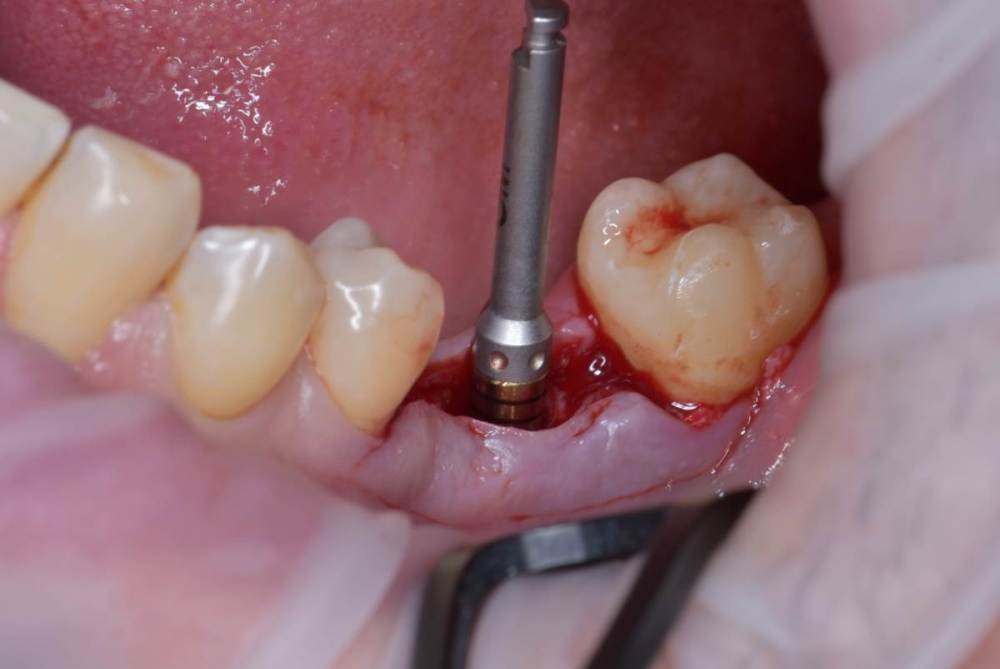

Fin Опубликовано 14 июля, 2023 Поделиться Опубликовано 14 июля, 2023 5 минут назад, TIGER сказал: @Doc спасибо ☺️ @Fin фиксировал мембрану Наверное я недопонимаю по данным фотографиям. На каком этапе Вы делали НКР? 1. Удаление 2.НКР+ импоантация? Ссылка на комментарий

TIGER Опубликовано 14 июля, 2023 Автор Поделиться Опубликовано 14 июля, 2023 @Fin 2 й этап имплант&нкр Ссылка на комментарий